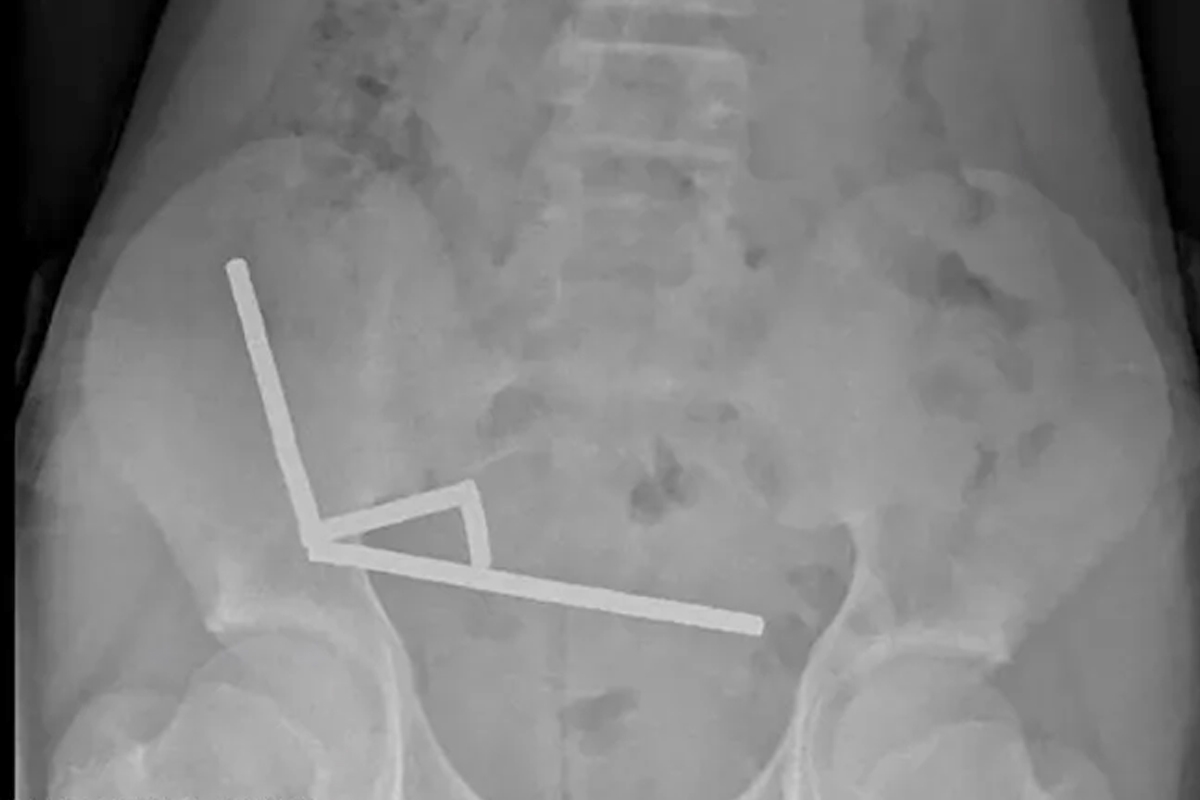

وأظهرت الأشعة أن المغناطيسات تكتلت معاً في 4 خطوط مستقيمة داخل أمعاء المراهق، ويبدو أنها كانت في أجزاء منفصلة من الأمعاء ملتصقة ببعضها بسبب القوى المغناطيسية.